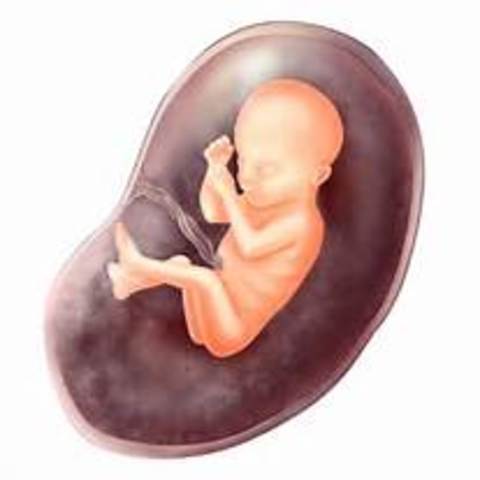

Week 12

The fetus is about 6 cm long! The fetus' face is starting to form more and insulin is produced by the pancreas to help the fetus move spontaneously.

• Week 13

Week 13

The fetus is now 3 inches long! It is also about 1 ounce in weight, due to bones forming over cartilage. The nose and chin and external genitalia are defined.